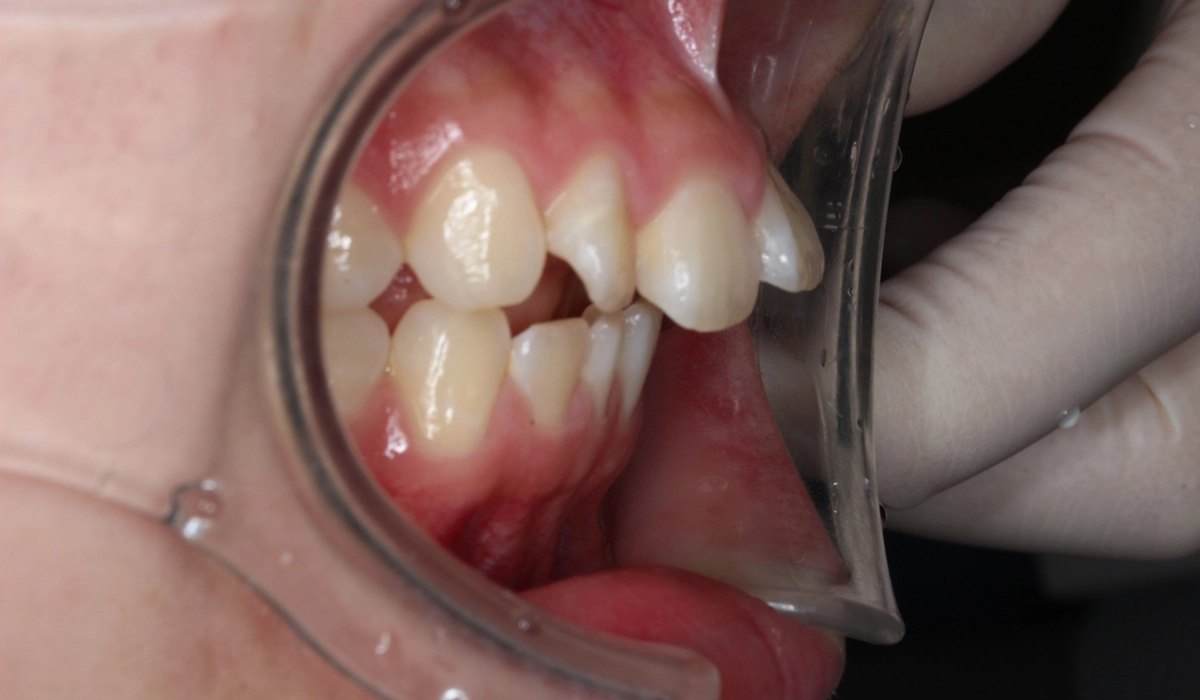

術前:オーバージェット

術後:オーバージェット